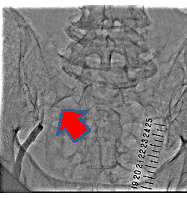

経皮的末梢動脈形成術の一例

- 【1】術前

- 【2】ワイヤー通過

- 【3】ステント留置

- 【4】術後